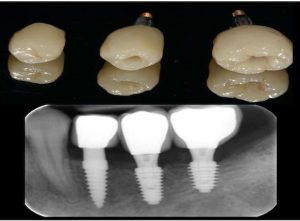

Dental Implants

When teeth are lost because of disease or an accident, dental implants may be a good option

Implant, Crown

Implant, Bridge, Crown

Implants